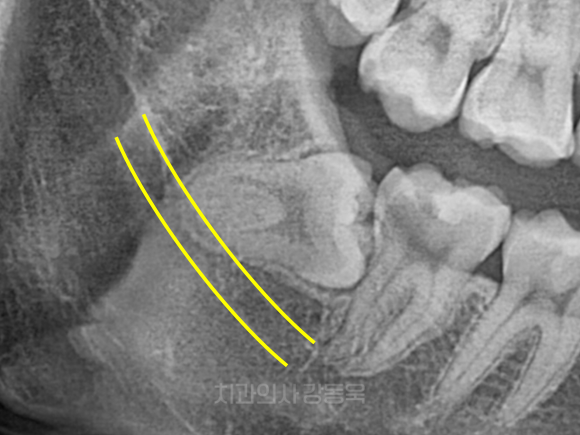

완전히 묻혀있는 사랑니

촬영일자: 2025.02.17

완전매복 사랑니 이해를 돕기 위한 참고 사진입니다.

참고사진과 같이,

겉으로는 보이지는 않지만

잇몸 안쪽에 숨어 있는 사랑니입니다.

겉으로는 보이지 않지만

갑자기 붓거나 통증이 생기고,

드물게 낭종이 생기는 경우도 있기 때문에,

정기적인 관찰이 중요할 수 있겠습니다.